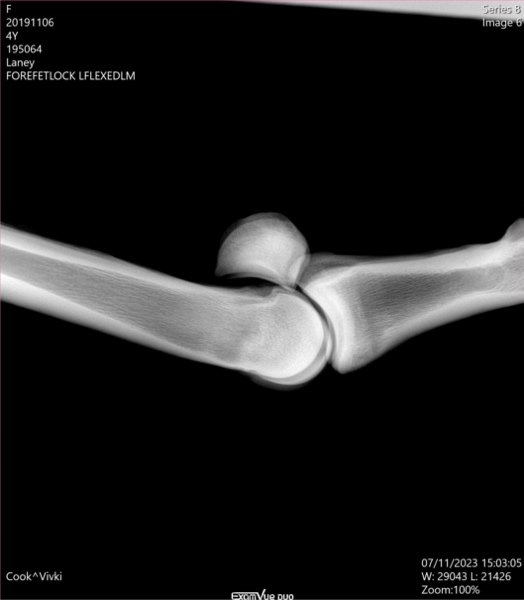

Samples of X-Rays